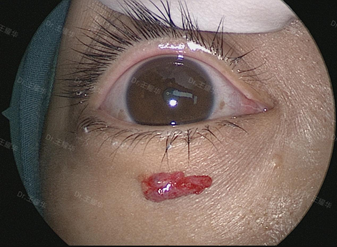

经过3小时的高精度奋战,肿瘤完整摘除。术毕,李女士的瞳孔大小与术前一致,标志着视神经功能得到最大程度的保护。

(摘除视神经管内海绵状血管瘤后,患者瞳孔大小正常)